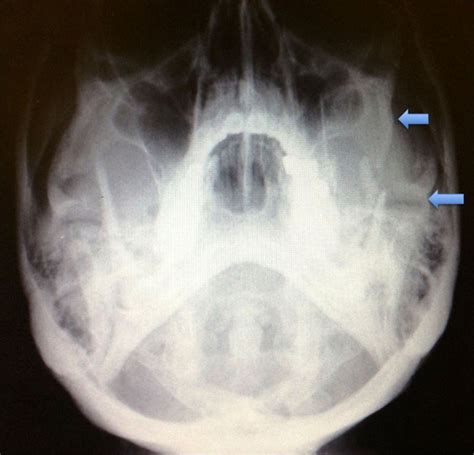

Interpreting the results of a Smv Zygomatic Arches Xray requires expertise in radiology. The radiologist looks for various indicators, including:

• Fractures: Visible breaks or displacements in the zygomatic arches.

• Tumors: Abnormal masses or growths that may affect the bone structure.

• Anomalies: Congenital or developmental issues that alter the normal anatomy of the zygomatic arches.

• Soft Tissue Involvement: Any signs of soft tissue damage or inflammation that may be associated with the zygomatic arches.

• Zygomatic Fractures: These are often the result of trauma and can range from minor cracks to severe displacements.

• Tumors and Cysts: Benign or malignant growths that affect the zygomatic arches.

• Developmental Anomalies: Conditions such as hypoplasia or hyperplasia of the zygomatic bones.

• Inflammatory Conditions: Infections or inflammatory processes that affect the zygomatic arches.